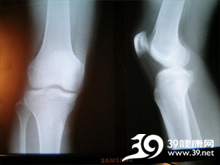

让孩子平卧,最下缘的肋骨超出身体的外缘,就叫做肋骨外翻。肋骨外翻是由于人的胸骨最下方的两条肋骨不是跟胸骨连在一块的,而且孩子在吸气呼气时的腹部运动幅度比较大,肋骨比较软的情况下会出现肋骨外翻的现象。婴儿肋骨外翻的原因有两个:一个是单纯的肋骨发育畸形;另一个原因就是佝偻病造成的。...